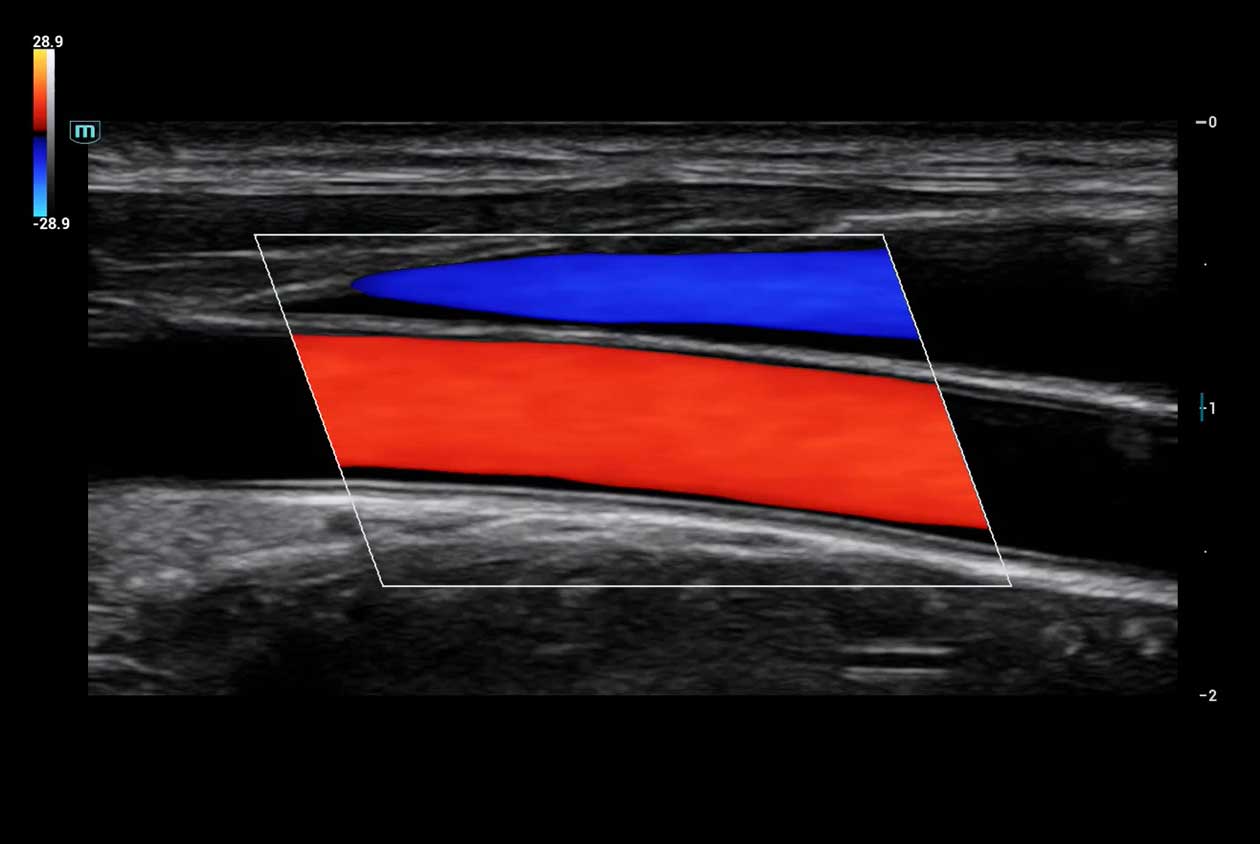

Clinical Images